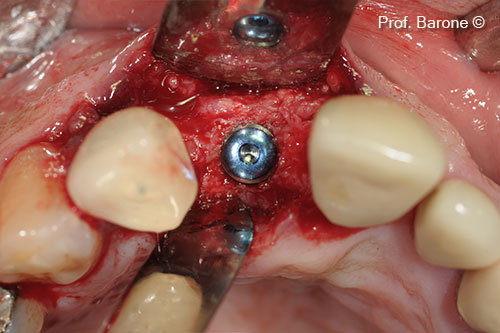

Cấy ghép implant vào sống hàm đã được tăng cường

Hình ảnh X-Quang quanh chóp răng 3 tháng sau khi cấy ghép implant